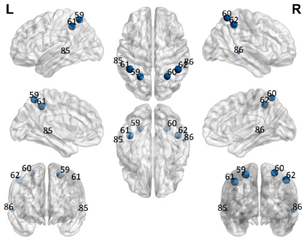

2.5. Regions of Interest

| DMN Partial | DMN Anterior | DMN Ventral | Sensorimotor | Visual | |||||

|---|---|---|---|---|---|---|---|---|---|

| Number in the AAL90 Atlas | Region Name | Number in the AAL90 Atlas | Region Name | Number in the AAL90 Atlas | Region Name | Number in the AAL90 Atlas | Region Name | Number in the AAL90 Atlas | Region Name |

| 59 | Parietal_Sup_L | 29 | Insula_L | 35 | Cingulum_Post_L | 1 | Precentral_L | 43 | Calcarine_L |

| 60 | Parietal_Sup_R | 30 | Insula_R | 36 | Cingulum_Post_R | 2 | Precentral_R | 44 | Calcarine_R |

| 61 | Parietal_Inf_L | 31 | Cingulum_Ant_L | 37 | Hippocampus_L | 7 | Frontal_Mid_L | 45 | Cuneus_L |

| 62 | Parietal_Inf_R | 32 | Cingulum_Ant_R | 38 | Hippocampus_R | 8 | Frontal_Mid_R | 46 | Cuneus_R |

| 85 | Temporal_Mid_L | 87 | Temporal_Pole_Mid_L | 39 | ParaHippocampal_L | 19 | Supp_Motor_Area_L | 47 | Lingual_L |

| 86 | Temporal_Mid_R | 88 | Temporal_Pole_Mid_R | 40 | ParaHippocampal_R | 20 | Supp_Motor_Area_R | 48 | Lingual_R |

| 55 | Fusiform_L | 57 | PostcentralL | 49 | Occipital_Sup_L | ||||

| 56 | Fusiform_R | 58 | Postcentral_R | 50 | Occipital_Sup_R | ||||

| 65 | Angular_L | 63 | SupraMarginal_L | 51 | Occipital_Mid_L | ||||

| 66 | Angular_R | 64 | SupraMarginal_R | 52 | Occipital_Mid_R | ||||

| 67 | Precuneus_L | 69 | Paracentral_Lobule_L | 53 | Occipital_Inf_L | ||||

| 68 | Precuneus_R | 70 | Paracentral_Lobule_R | 54 | Occipital_Inf_R | ||||